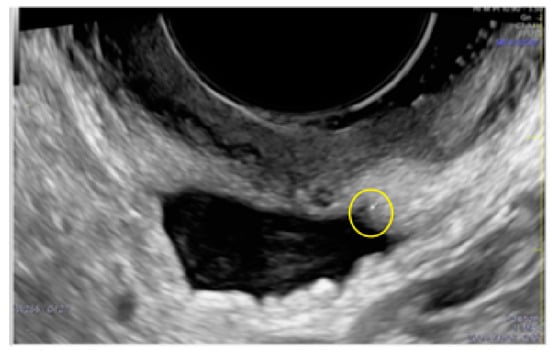

- The presence of hyperechoic foci (we called this a “pearl”).